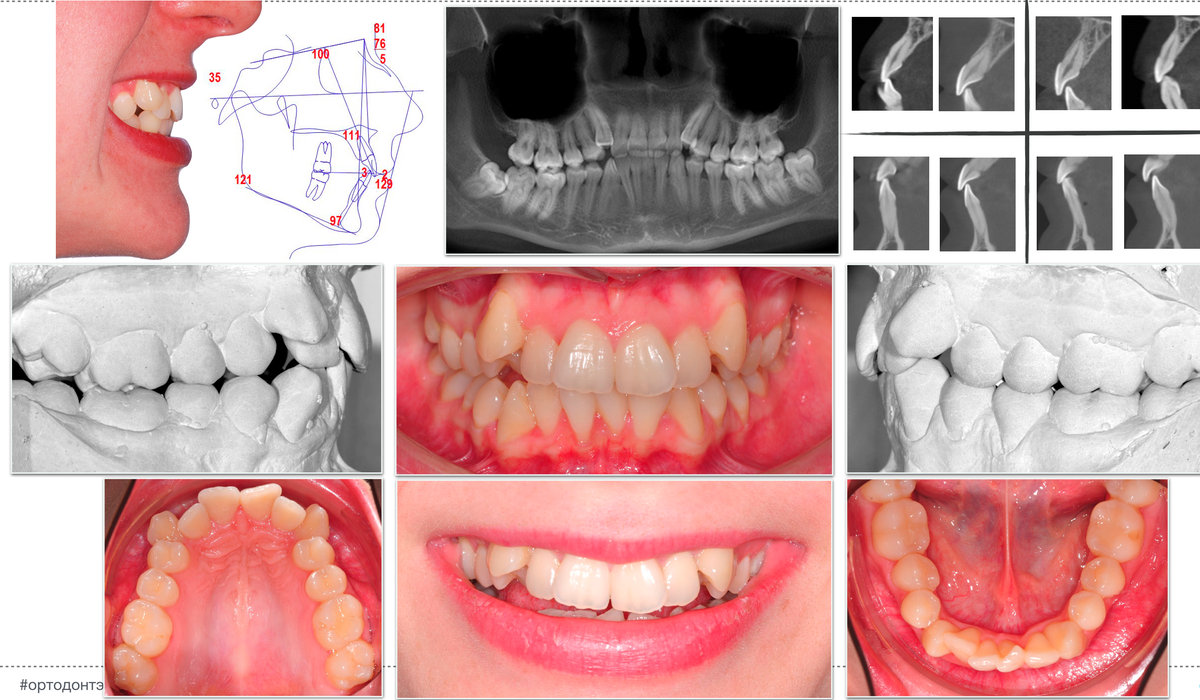

Маленький фрагмент этого клинического примера видели активные подписчики нашего блога в Инстаграм, а также участники Школы ортодонтии на уровне 3.

Но видели лишь в части усеченной диагностики и логики принятия решения об удалении.

В рамках вебинара мы разберем его полностью:

- дефицит места на верхнем и нижнем зубных рядах

- значительное смещение нижнего центра

- очень компромиссный пародонт

- короткие корни центральных резцов

- асимметричные классы